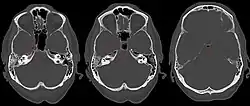

| Apicitis petrosa as seen in computed tomography | |

In persons with longstanding ear infection and typical symptoms, medical imaging such as CT or MRI of the head may show changes that confirm disease involvement of the petrous apex of temporal bone.